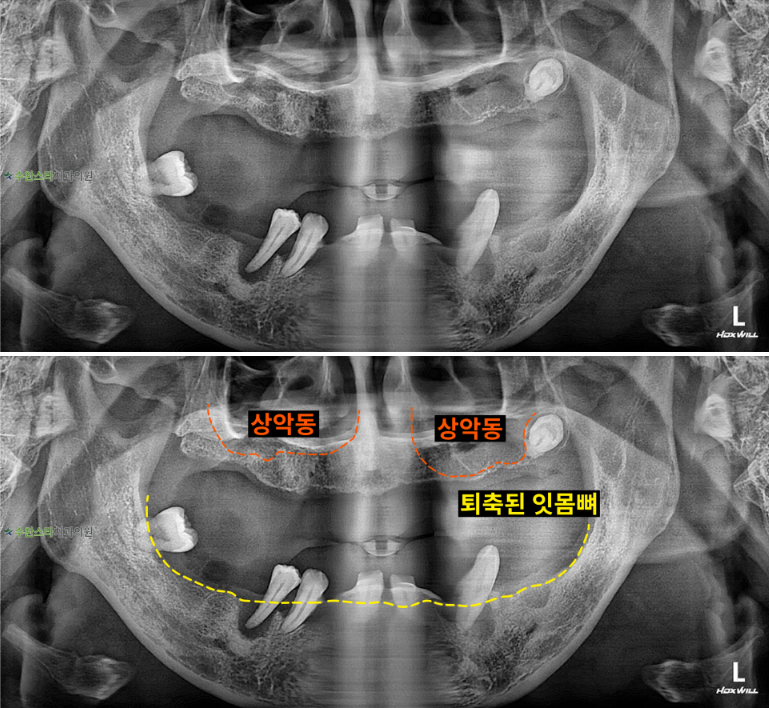

내원 시 파노라마

처음 내원 시 파노라마, 40대 남성 (2025. 11 촬영)

내원 시 파노라마 사진입니다.

위아래 잇몸뼈가

위 아래 모두 많이 퇴축된 모습이라

자연치아를 살릴 수 없어

발치 후 뼈 이식과 임플란트가

필요합니다.